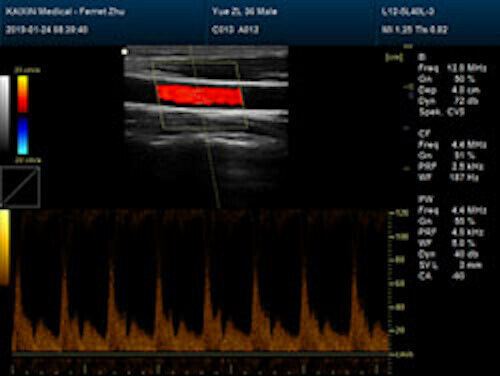

| Rich clinical application function • B+CF (Dual Images) • B+CF/PDI/DPDI+PW (Triplex) • Convex extended imaging technology • Linear array deflection/Trapezoidal imaging technology • Spatial compound Imaging technology • Panoramic imaging technology (optional) • 3D/4D imaging technology (optional) • Speckle noise removal technology • Pulse inversion tissue harmonic imaging technology (iTHI) |